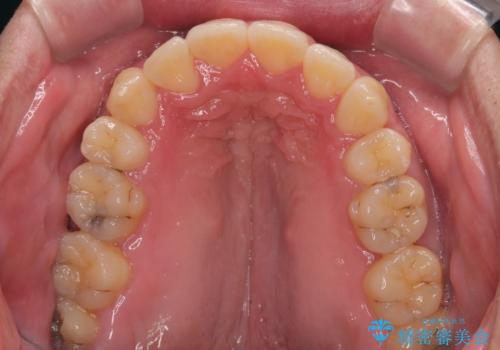

上下前歯の前後差が非常に大きく、3年以上の治療期間が予想されましたが、無事に3年間ちょうどで仕上げることができました。